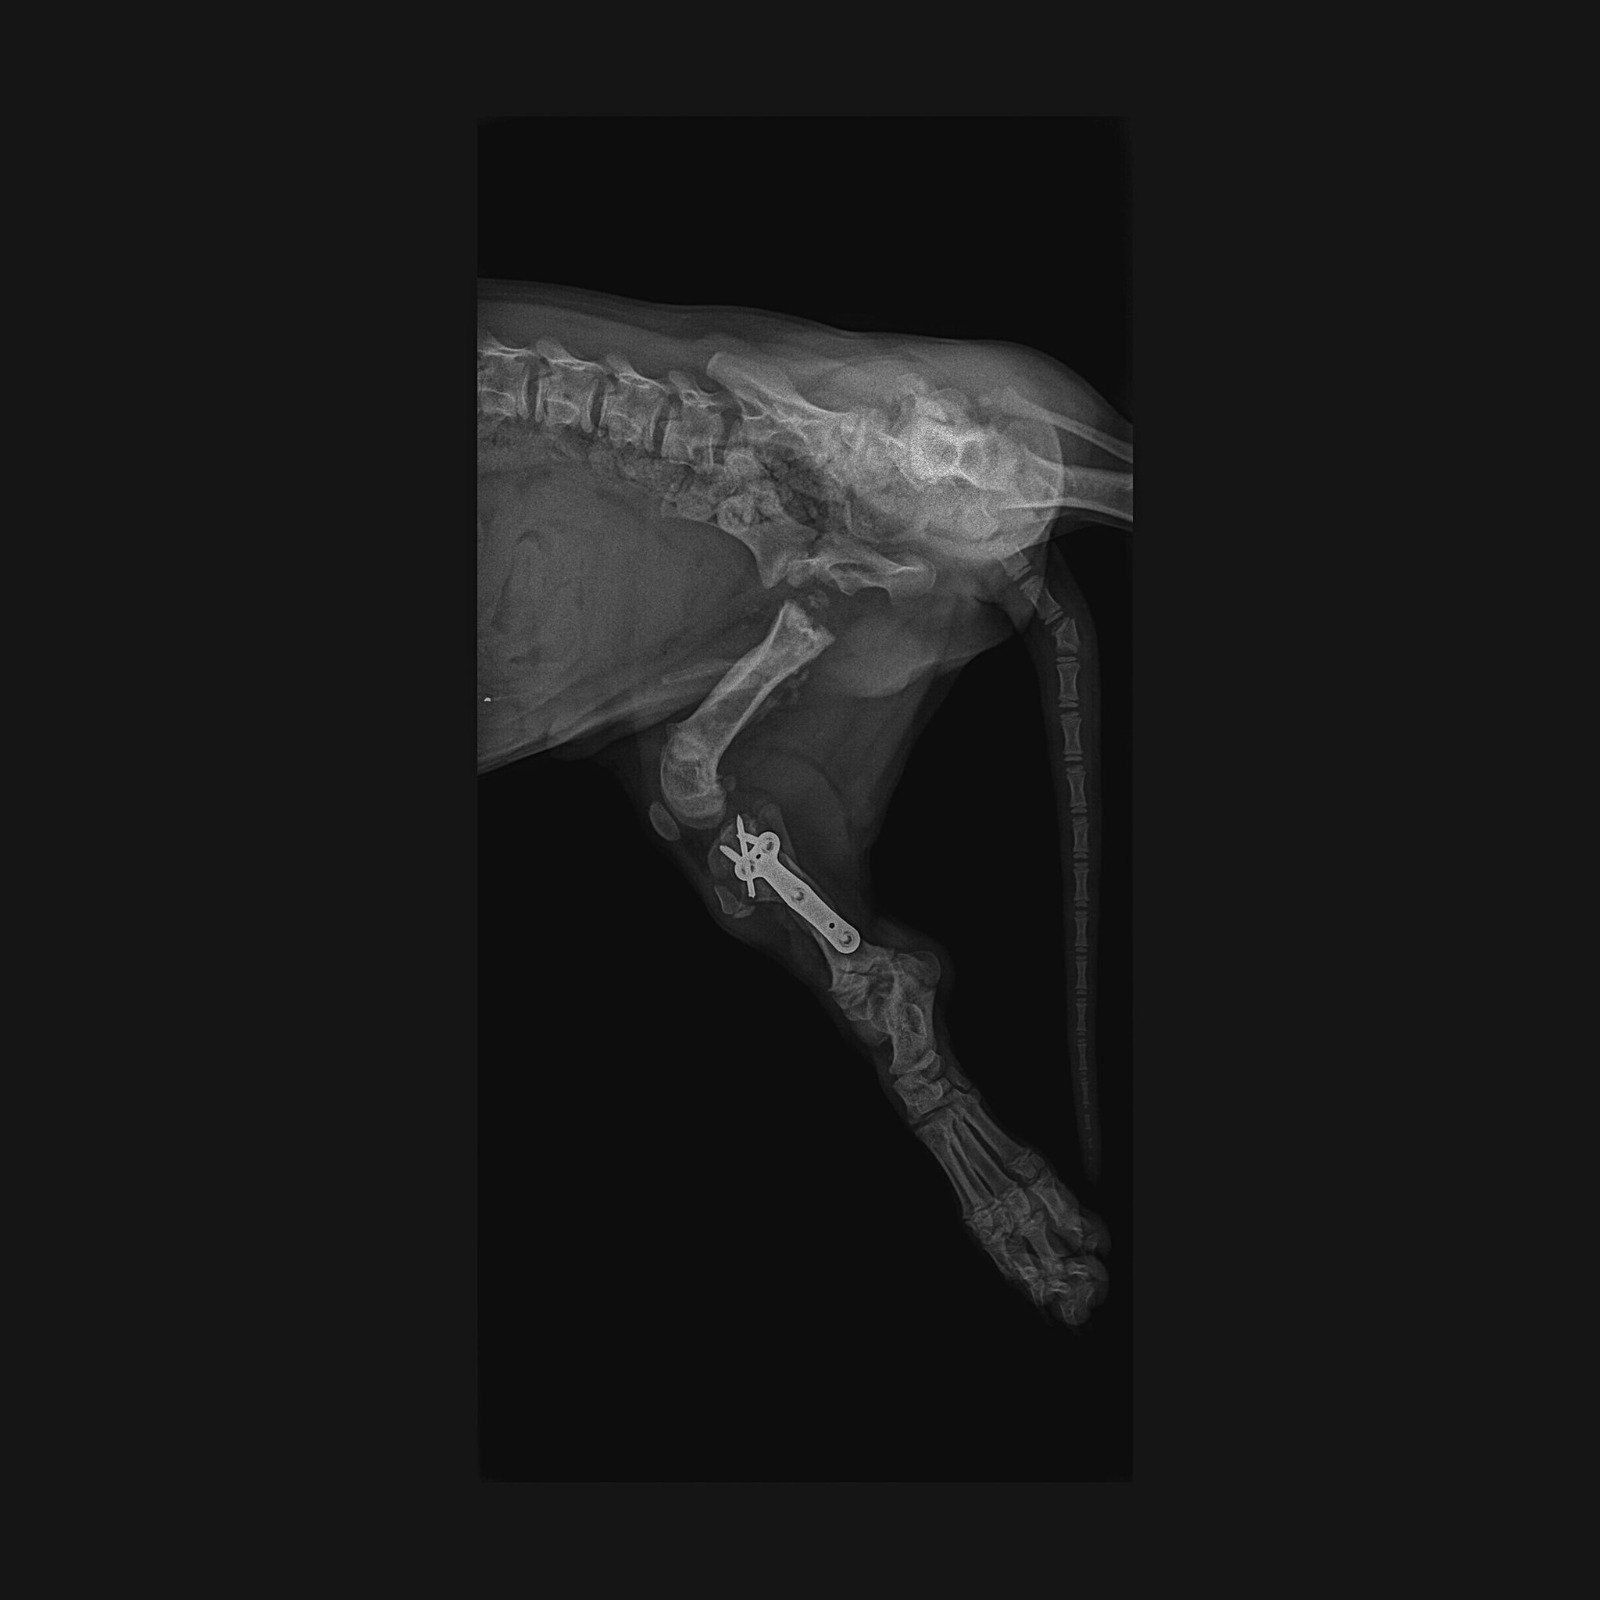

Vor etwas über drei Monaten fand man den kleinen Jungen unter einer Brücke...mit den Vorderläufen robbend schleppte er sich über den Boden...er war schwer verletzt und wie sich in der Tierklinik zeigte waren seine Hinterläufe gebrochen und auch sein kleines Becken hat etwas abbekommen. Vermutlich stürzte er von eben jener Brücke...oder er wurde sogar geworfen (was zum Bild und Art der Verletzungen passen würde)...nur er weiß was geschehen ist...

Er wurde operiert und wieder zusammengeflickt, ganze 3 Monate verbrachte er in der Tierklinik! Das ist die Hälfte seines bisherigen jungen Lebens!

Er wird noch einmal operiert werden müssen, das eingesetzte Metall muss wieder entfernt werden. Und dann, wenn auch das überstanden ist, würde sich der kleine Choco so sehr über seine ganz eigene Familie freuen.